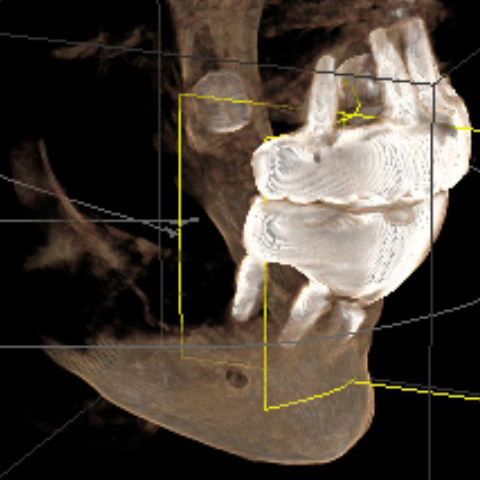

After reviewing CBCT and additional high definition xrays of each implant, a prosthodontist with 40 years experience wrote in his report:

"... the last implant on the lower right side has practically no bone, the last implant on the lower left has about 70-80% bone loss. Both implants should be removed. One implant in the middle is not being used ... "

There are several issues with all of the implants, from problems with their locations, problems with mismatched heights from one implant to another, problems with their depth requiring gum grafts as there is no attached gingiva, problems with two of the upper implants apparently touching each other per periodontist report, a few other issues, and all seem to have some level of bone loss around the implants.

The near total lack of bone at the right lower rear implant, and all the other problems with the implants, already existed when the first periodontist took a CBCT and xrays on October 9, 2024, less than one month after Bansal said everything was perfect. Clearly all those problems did not magically develop overnight.